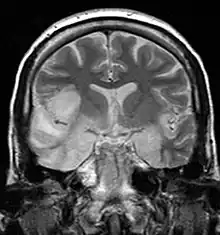

| Coronal T2-weighted MR image shows high signal in the temporal lobes including hippocampal formations and parahippogampal gyrae, insulae, and right inferior frontal gyrus. A brain biopsy was performed and the histology was consistent with encephalitis. PCR was repeated on the biopsy specimen and was positive for HSV | |

Most individuals with HSE show a decrease in their level of consciousness and an altered mental state presenting as confusion, and changes in personality. Increased numbers of white blood cells can be found in patient's cerebrospinal fluid, without the presence of pathogenic bacteria and fungi. Patients typically have a fever[1] and may have seizures. The electrical activity of the brain changes as the disease progresses, first showing abnormalities in one temporal lobe of the brain, which spread to the other temporal lobe 7–10 days later.[1] Imaging by CT or MRI shows characteristic changes in the temporal lobes (see Figure). After the first symptoms appear, patients might lose their sense of smell. This can also be accompanied by the inability to read, write, or speak coherently, and understand verbal speech.[6]